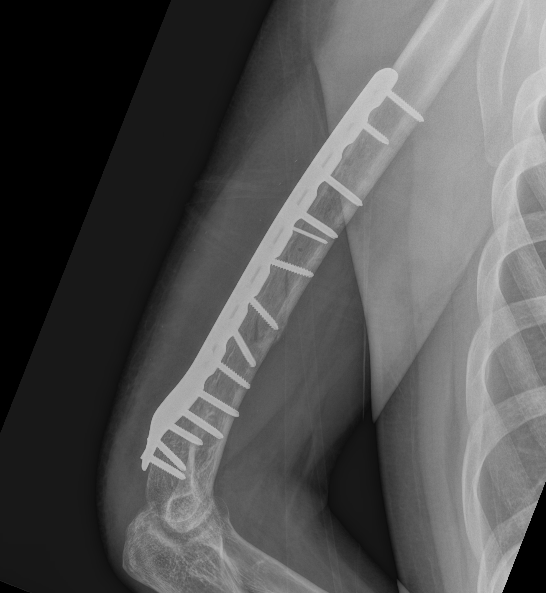

Humeral Fracture SegmentalHumeral Plate LateralHumeral Plate Long AP

Segmental fracture ORIF